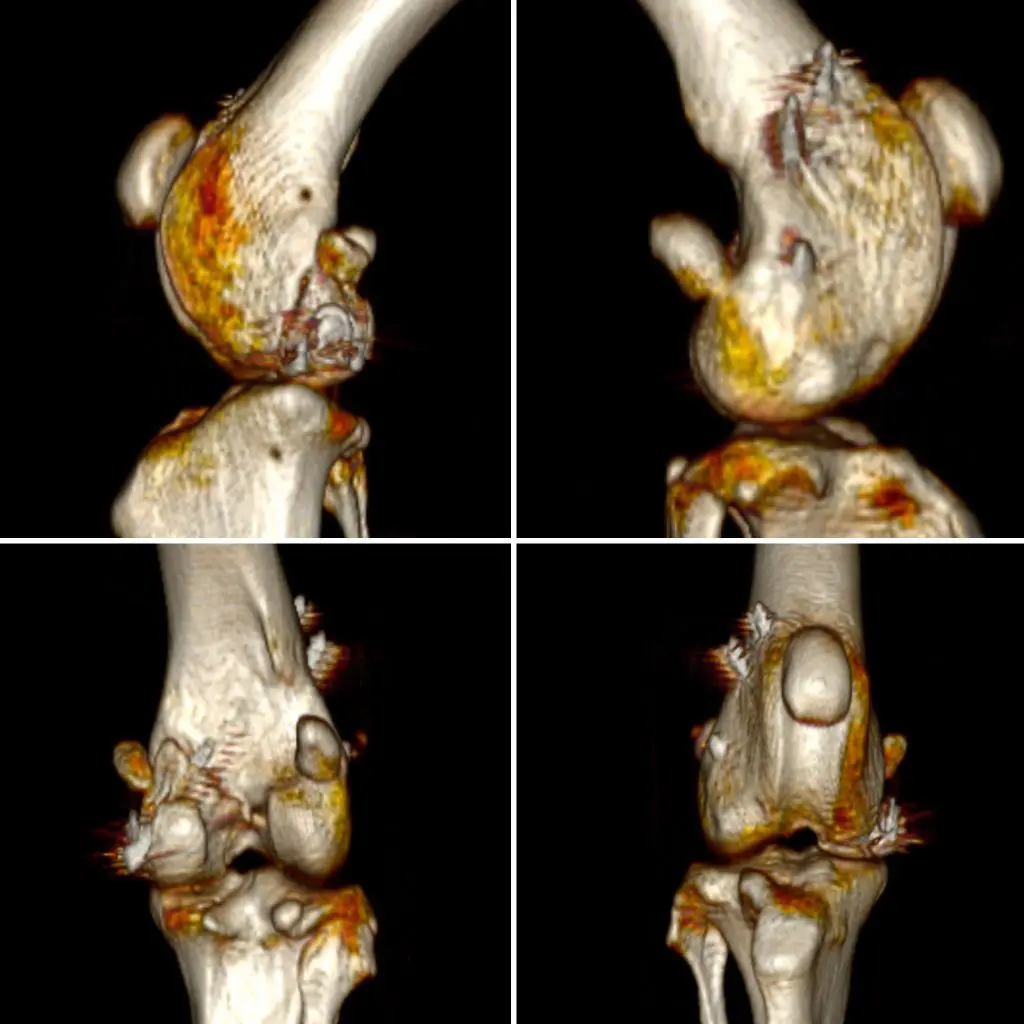

El tratamiento fue quirúrgico y consistió en la reducción anatómica y estabilización de los fragmentos óseos. Se coloca un tornillo con arandela y agujas de Kirschner. Todo el procedimiento se realizó con asistencia de fluoroscopia intraoperatoria, lo que nos permitió garantizar una colocación precisa y óptima de los implantes, respetando la congruencia articular.

El resultado quirúrgico fue muy satisfactorio. Tras unas pocas semanas de reposo y control postoperatorio, SENDA mostró una evolución excelente, recuperando progresivamente la funcionalidad del miembro. Una vez comprobado que se encontraba clínicamente estable y que las radiografías evidenciaban una correcta cicatrización ósea, le dimos el alta médica.